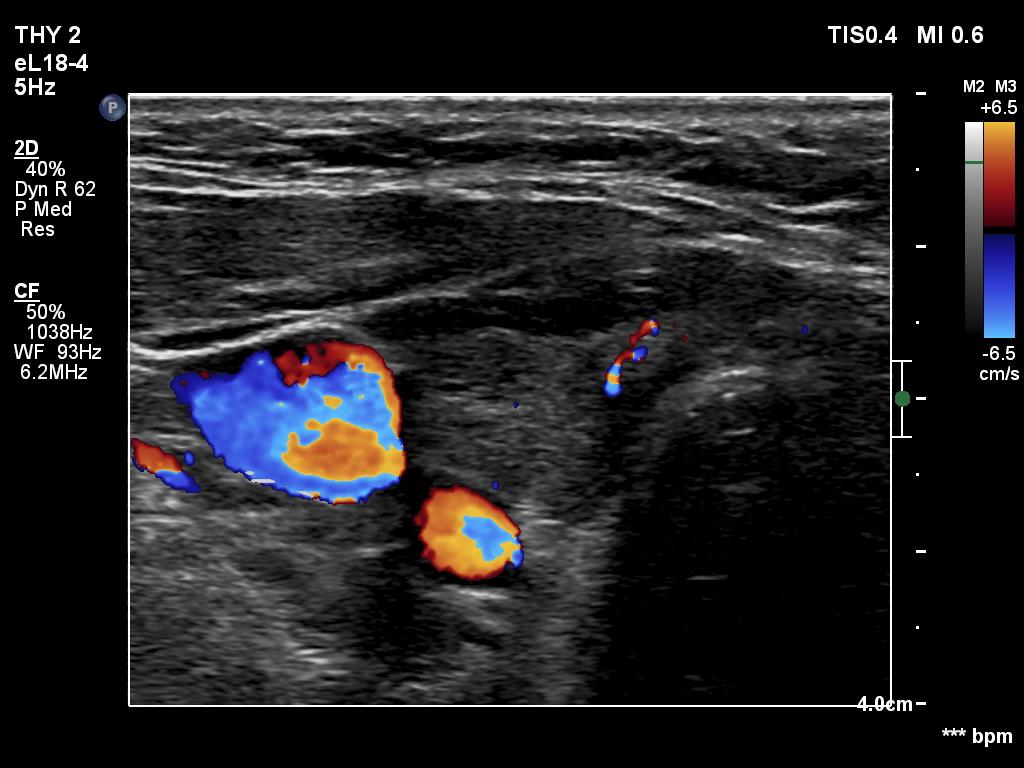

Ultrasonography. The thyroid was hypoechogenic. There was an iso/hyperechoic nodule in both the right and left lobes. The nodule in the left lobe had perinodular vascularity. The dimensions of the nodule in the left lobe were 20x18x31 mm, width, depth, length, respectively. This means that the volume of the nodule has increased almost 8-fold in 10 years.